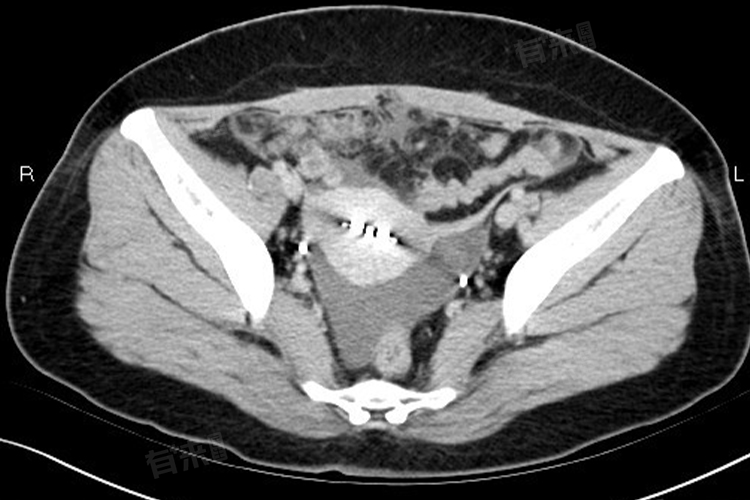

盆腔积液增多时,治疗方法需根据其病因和病情严重程度来选择,如针对生理性盆腔积液,可能不需要治疗,而针对盆腔炎导致的盆腔积液可能需要进行抗炎治疗。

如果发现盆腔积液增多,且伴有腹痛、发热、白带异常等不适症状,应及时就医,进行详细检查,明确病因后进行针对性治疗。